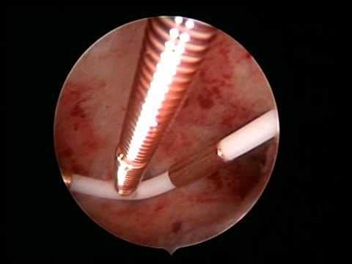

Hysteroscopy showing Submucus Fibroid in Uteruine Cavity.

Three-Dimensional Ultrasonography (3D USG) in comparison to hysteroscopy is less invasive, cheaper, easily accepted by most patients and does not require much training. In most cases an endometrial polyp can be differentiated from the submucous fibroid based on the imaging characteristics. The polyps are typically round in shape, smooth in outline, and are generally echogenic, compared to the endometrium or are isoechoic to it. The underlying endometrial-myometrial interface is preserved (Figure 5). Moreover the presence of a vascular pedicle has a positive predictive value of up to 81.3%. Fibroids are more inhomogeneous, hypoechoic, and there is a loss of endometrial-myometrial interface. The percentage of the intra cavitary portions of the submucous fibroids i.e., grade of submucous myoma can be assessed on 3D USG by the degree of distortion caused by it (Picture 6).